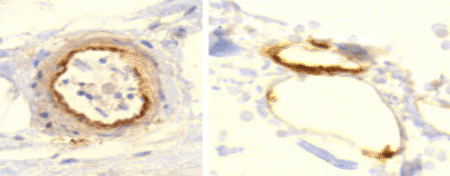

Oga-valgu ekspressioon väikeste veresoonte seintes

Me näeme oga-valgu ekspressiooni arterioolides (väikesed arterid; vasakul), samuti veenides (väikesed veenid) ja kapillaarides (paremal). Ekspressioon on kõige silmatorkavam sisemises rakukihis, endoteelis. See muudab endoteelirakud immuunsüsteemi rünnaku jaoks “pardid”.